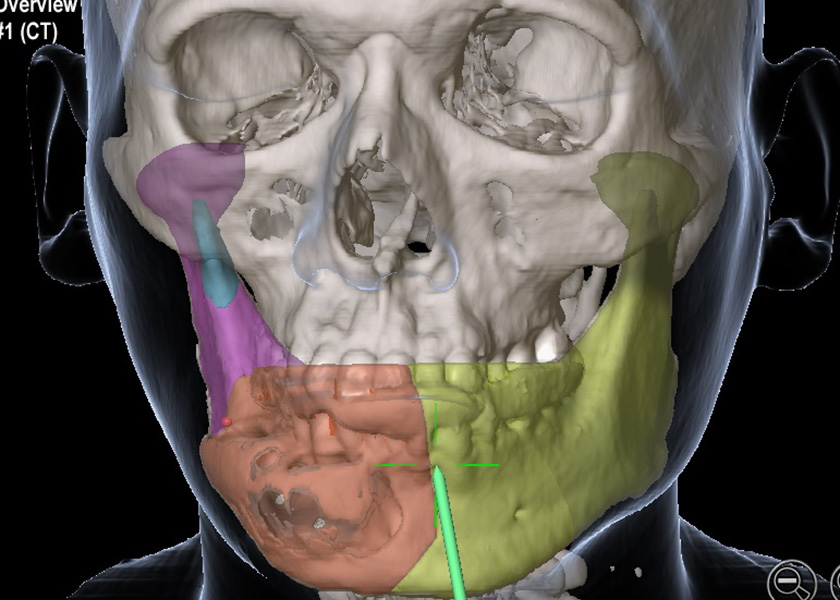

CT画像解析ソフトウェアの普及に伴って、顎骨に生じた様々な疾患に対するコンピュータ画面上での手術シミュレーションが可能となっています。しかし、コンピュータの画面で顎骨の切除に伴う形態の変化、骨片の変位あるいは咬合の変化などをシミュレーションシステムで詳細に解析したとしても、実際の手術にその結果を反映させることは困難です。

そこで、私たちは手術ナビゲーションシステムを導入し、顎変形症に対する顎矯正手術、顎骨腫瘍切除手術などに用いています。術前の手術シミュレーションとナビゲーションを組み合わせることによって、より正確で安全な手術を行うことが可能となります。